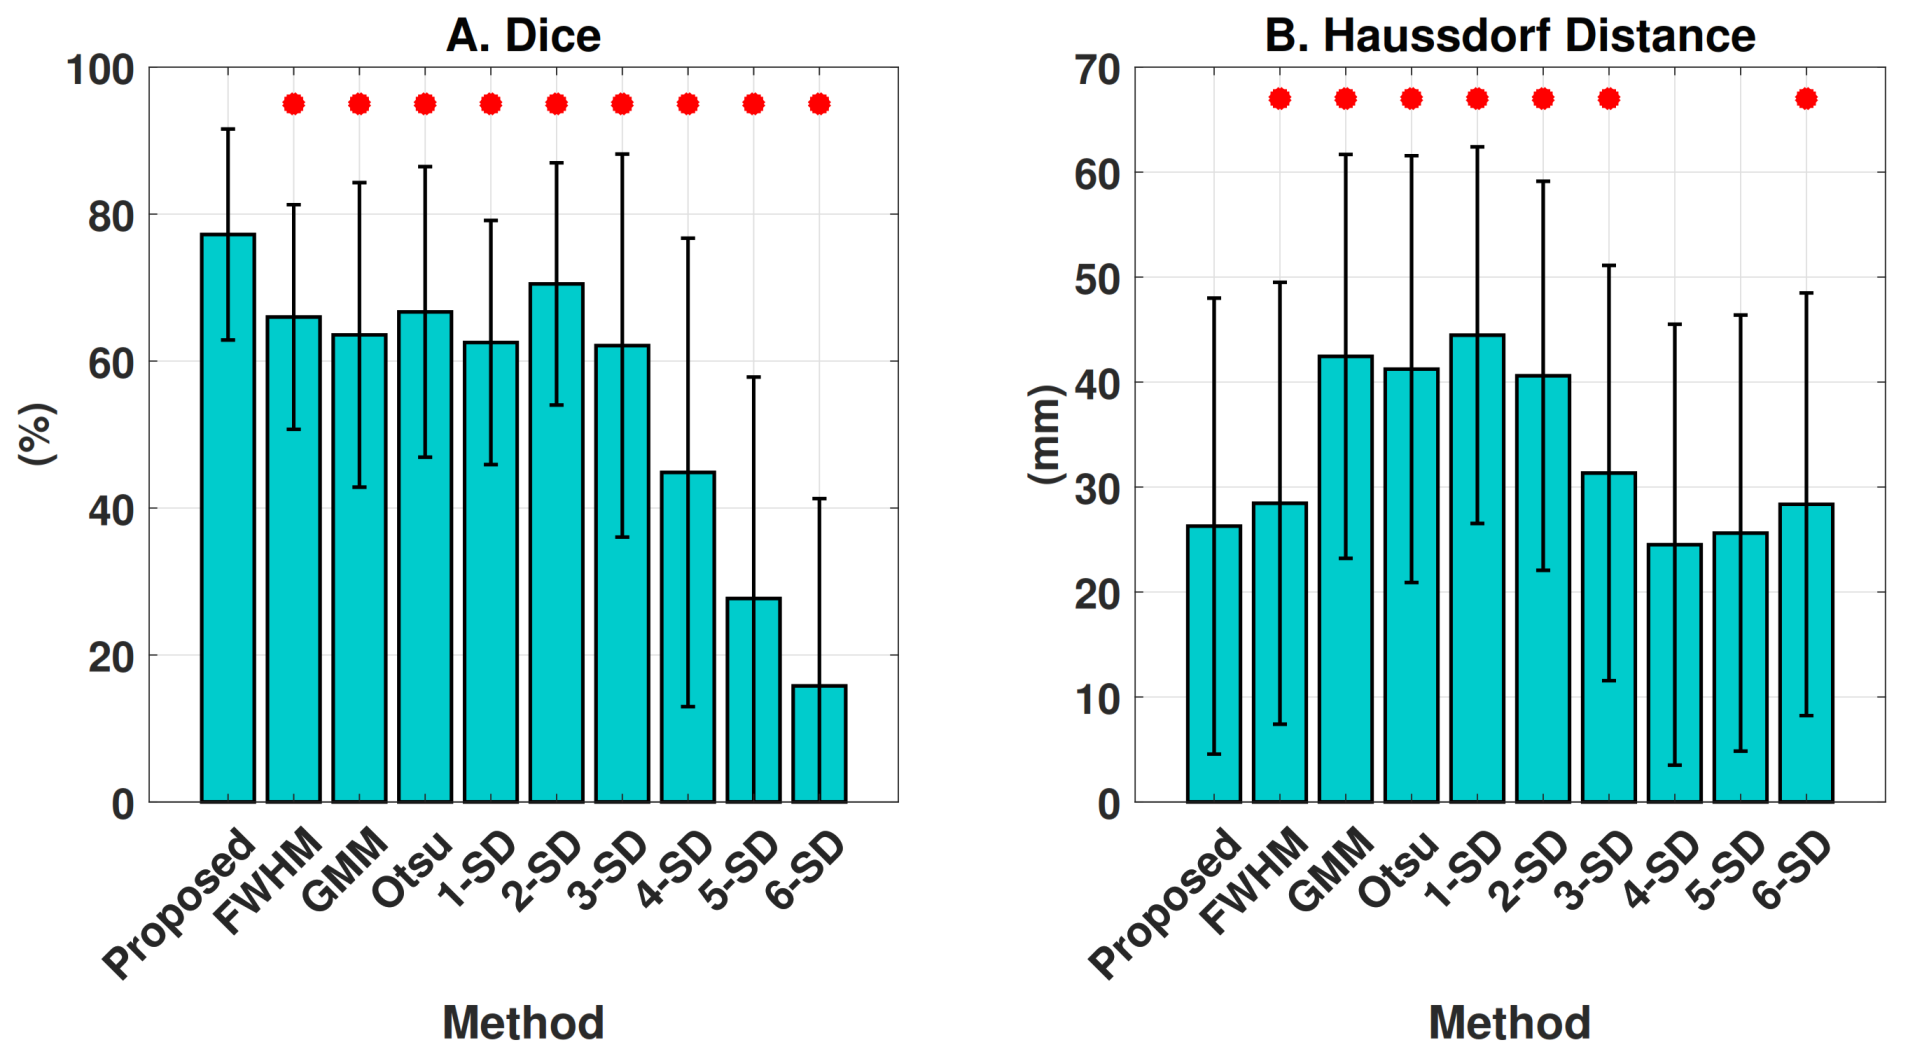

4.2.3. Microvascular Obstruction Inclusion

3.2.6. Comparison against Previous Methods